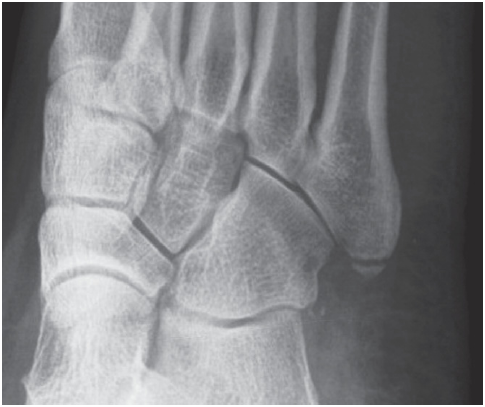

다음은 제5중족골 골절의 네 가지 방사선 영상이다. 손상은 무엇인가?

제5중족골 기저부 골절 (Fractures of the Fifth Metatarsal Base)

① 족저근막의 외측열 부착부의 견열 골절

② 단비골건 부착부의 견열 골절

③ 존스 골절(Jones fracture)

제5중족골 감입 골절(impaction fracture)로, 피로 골절으로 종종 시작된다.

④ 손상 부위 없음

이는 제5중족골 기저부의 정상적인 발달성 골돌기(apophysis)에 해당한다.